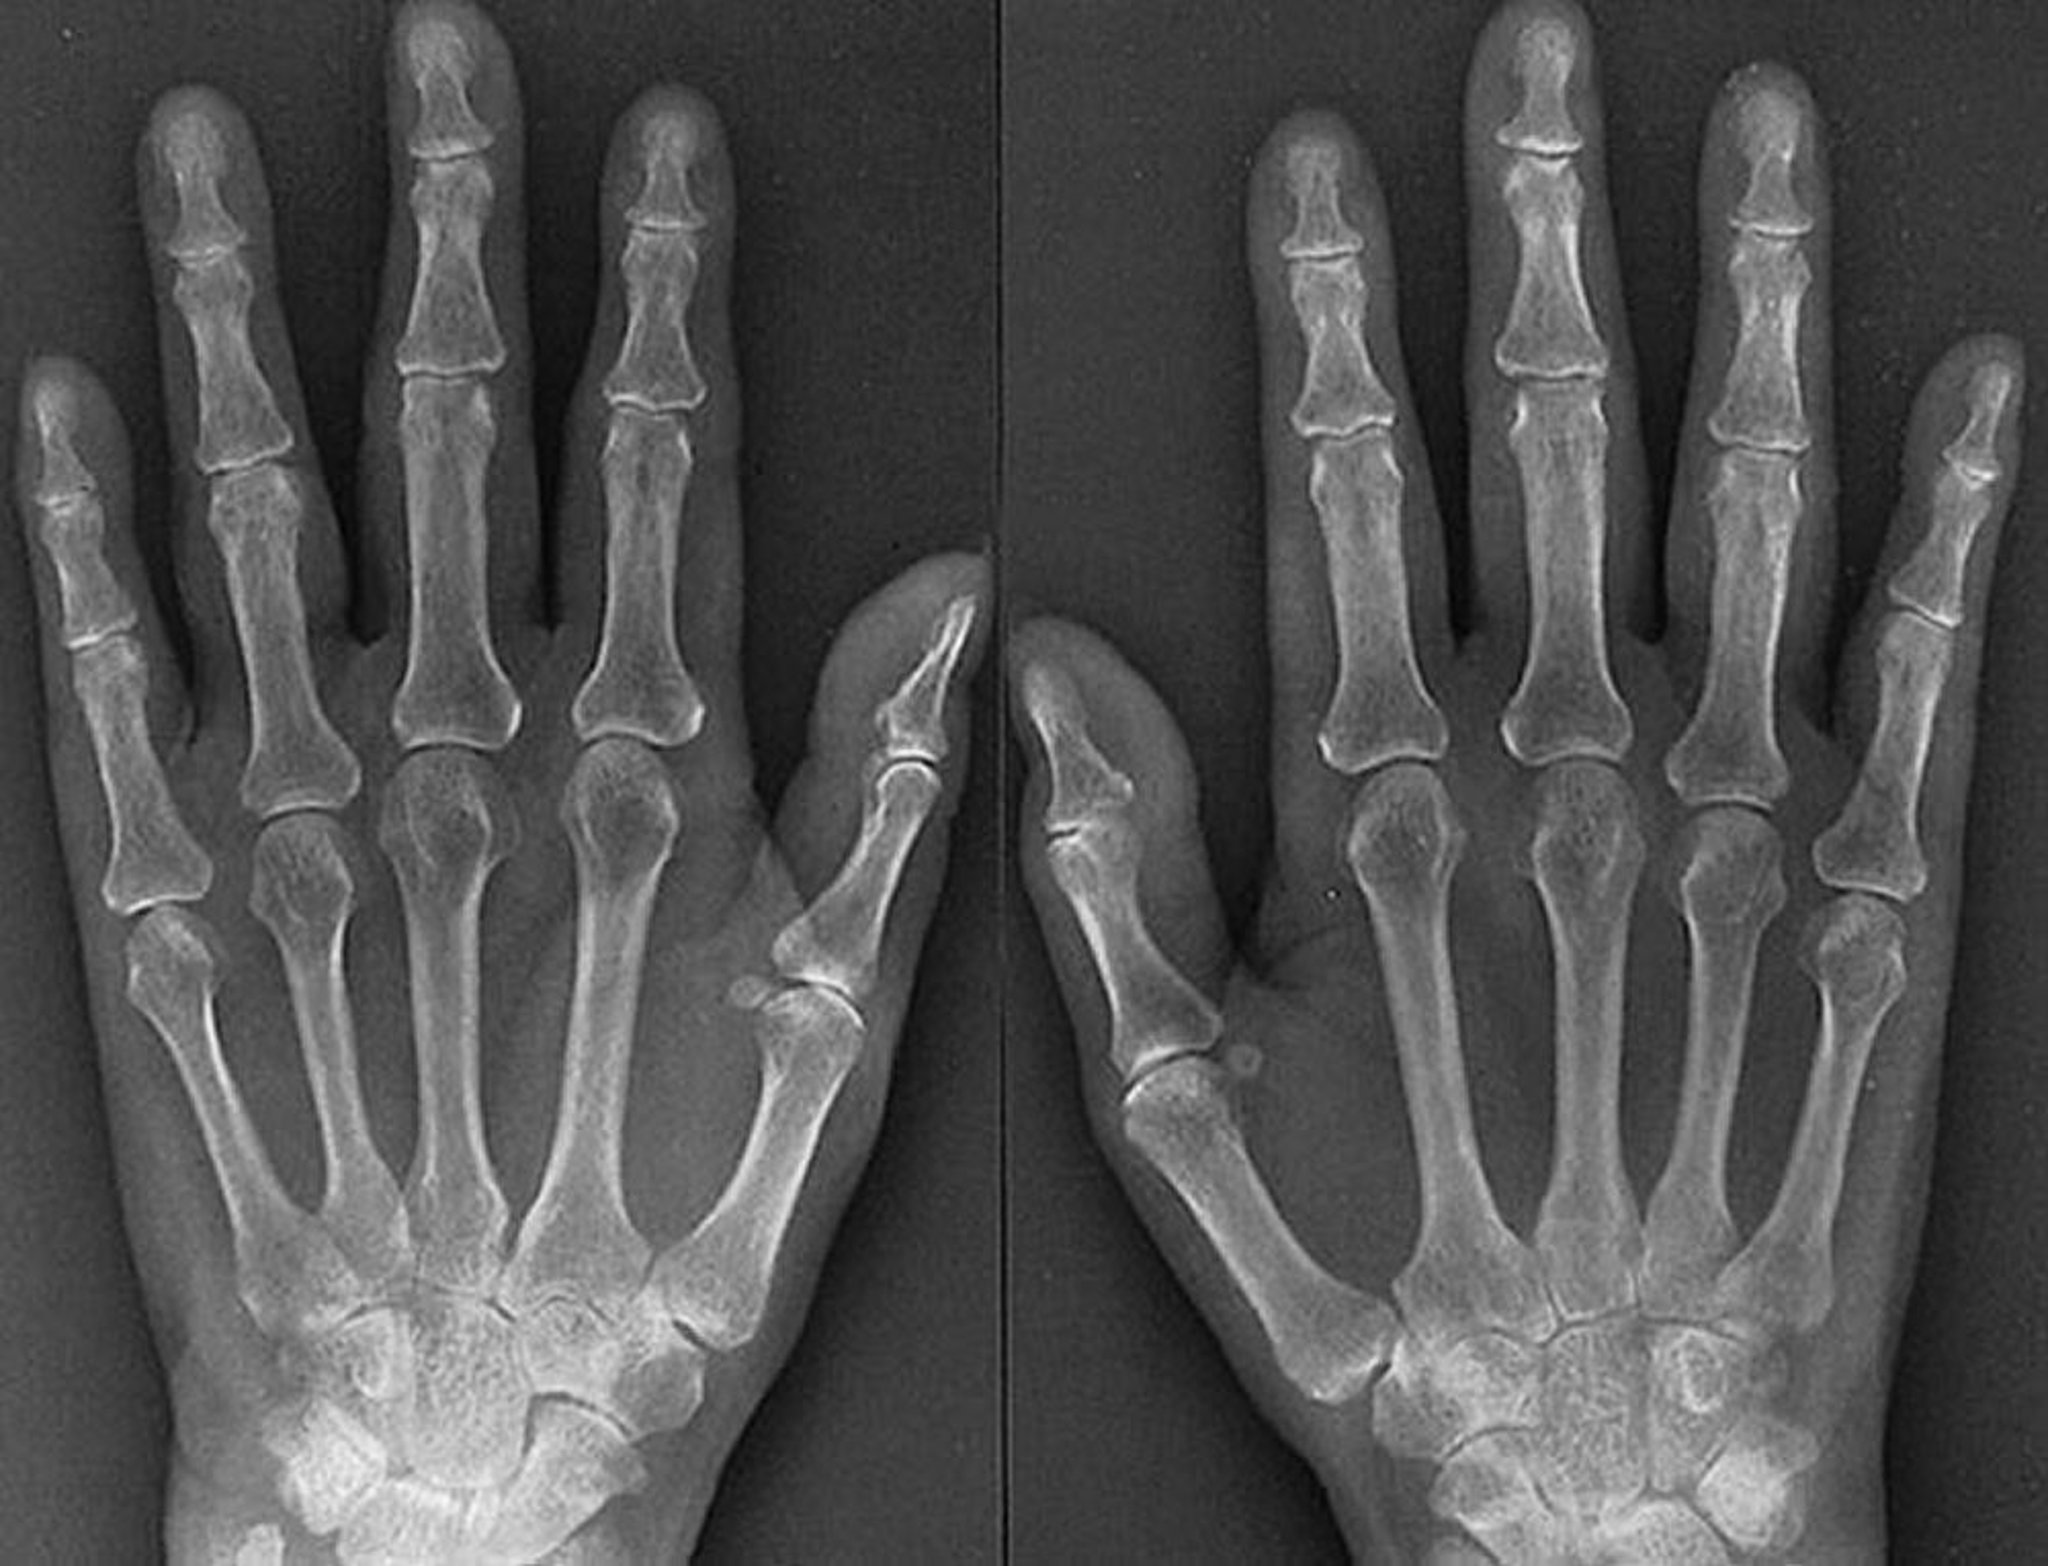

早期関節リウマチのX線の特徴

関節リウマチを患って1年の61歳女性のこのX線では,進行が速い関節リウマチの早期の特徴として,中手指節関節および近位指節間関節の軟部組織の腫脹,関節周囲の骨粗鬆症,両手の複数の中手指節関節および近位指節間関節における対称性の関節裂隙の狭小化,ならびに右の第3および左右の第4中手指節関節のわずかなびらんの所見などがみられる。